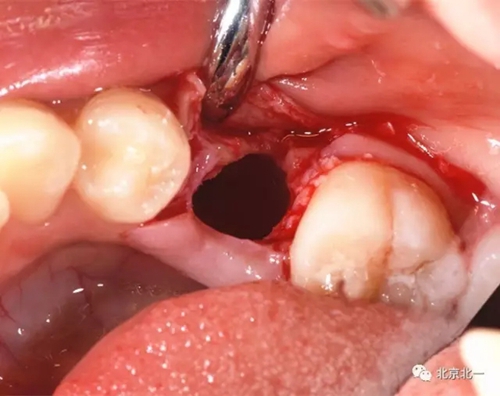

拔牙前臨床照片

術(shù)中有絲分裂

埋伏牙專用攪碎機(jī)攪碎牙齒